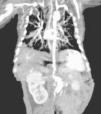

Al realizar ecocardiogramas de control por la patología cardiaca de base, se nota la dilatación en aorta, siendo más evidente en la 3.a semana de vida, debido a este hallazgo se decide la realización y confirmación en angio-TC (fig. 2).

Durante la realización del primer ecocardiograma doppler se observa dilatación de aorta descendente, corroborado en estudio ecocardiográfico posquirúrgico de reparación de DAP, con aneurisma en arco aórtico posterior a la arteria subclavia así como presencia de trombo de 4x3cm en la desembocadura de vena cava superior; se realiza angiotomografía en la cual se observa aneurisma a nivel aórtico, probable coartación aórtica, además de aneurisma en aorta abdominal (fig. 1). Al momento del diagnóstico se encuentra con recuento leucocitario y plaquetario normal, anemia, hipocomplementemia a expensas de C3, PCR positiva y factor VIII aumentado.